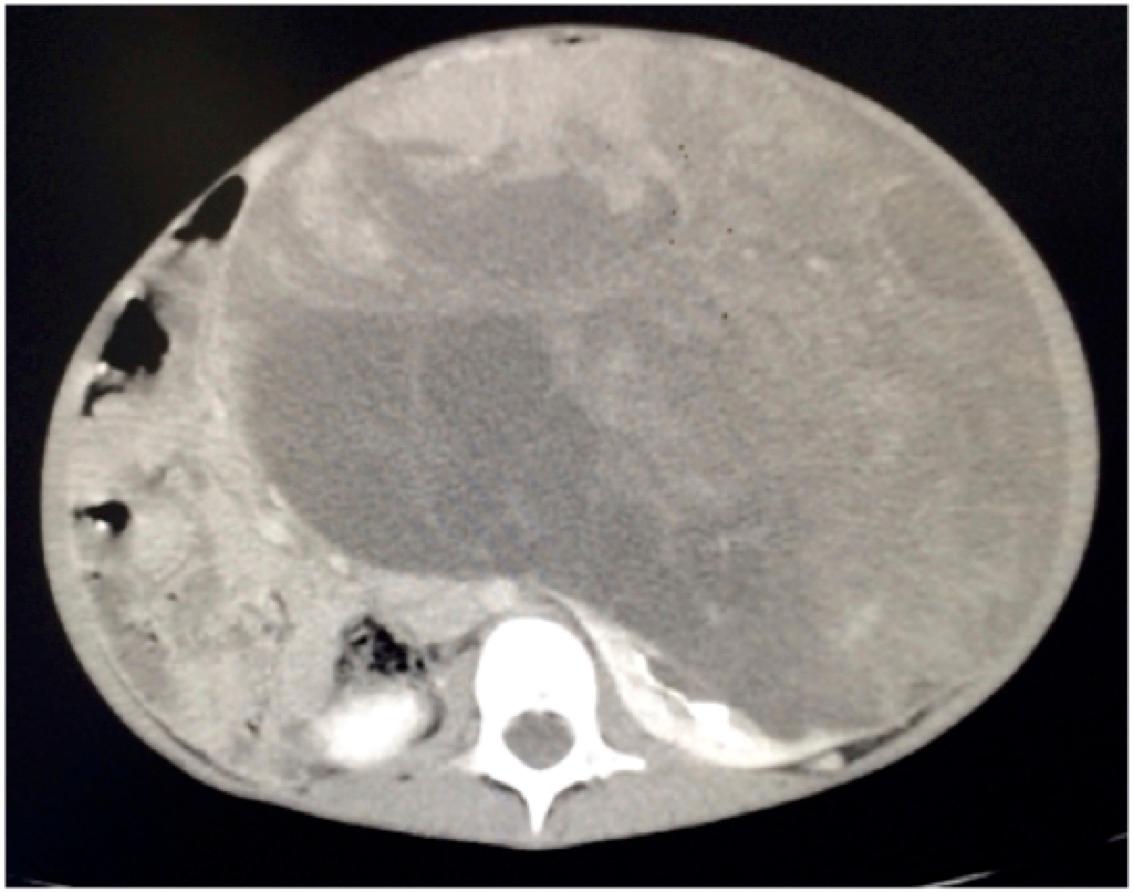

The next step in the management of this patient is: